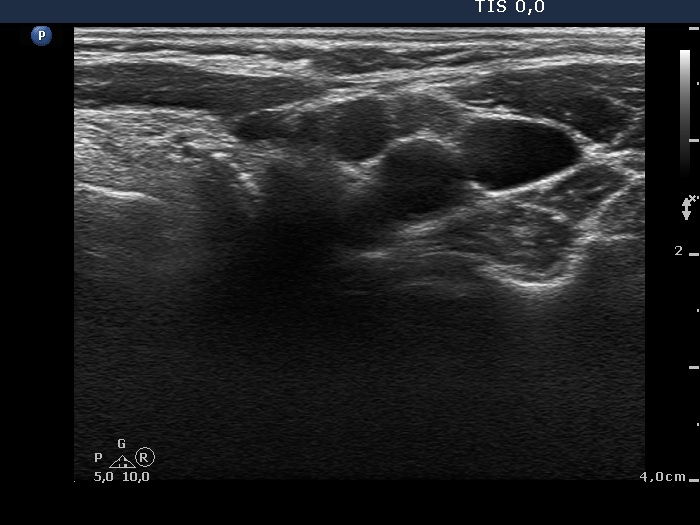

Ultrasonography: We could not find thyroid parenchyma. A small lymph node was present lateral to the left thyroid bed. The hilum was absent.